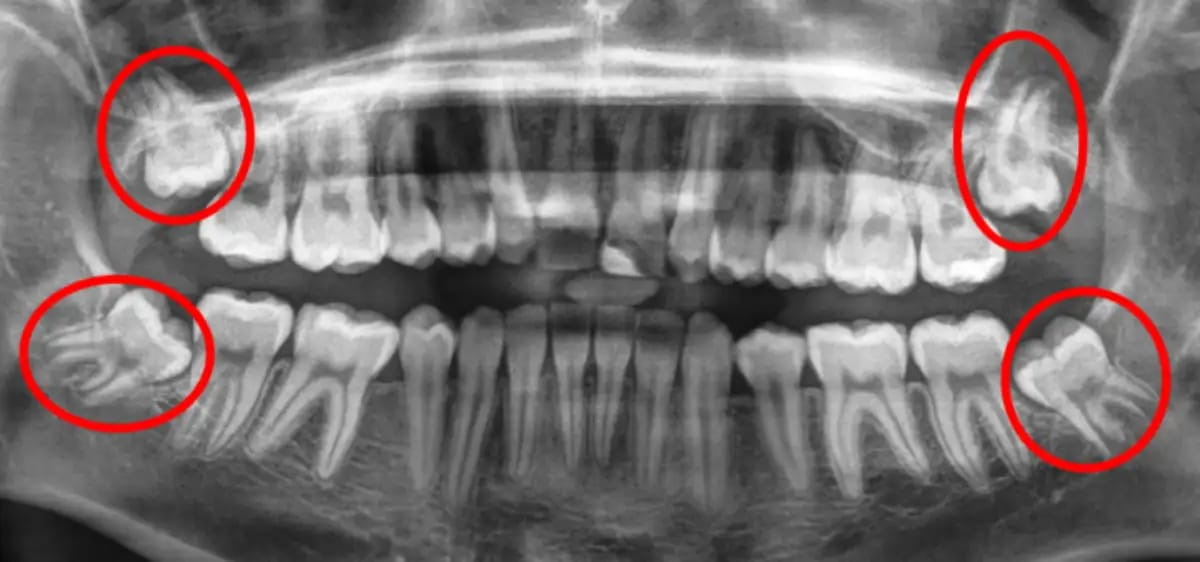

Impaksi gigi adalah sebutan untuk gigi yang tidak bisa tumbuh sehingga tertanam di dalam gusi, baik sebagian maupun sepenuhnya. Kondisi ini cukup sering terjadi dan umumnya tidak menimbulkan rasa nyeri. Impaksi gigi paling sering dialami oleh gigi bungsu (gigi yang tumbuh terakhir saat seseorang dewasa). Untuk pendaftaran SEKDIN/POLRI/TNI  gigi impaksi kategori stekes 4 gugur. Lakukan operasi bedah mulut gigi impaksi. Konsultasikan dengan kami dengan proses cepat tanpa antri dan biaya sangat terjangkau